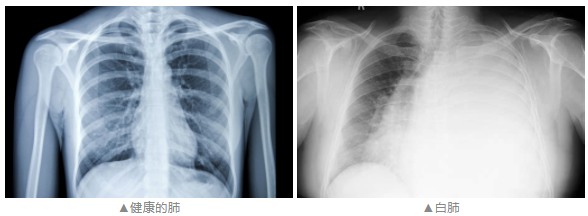

而咱们担心的那种情况,是孩子生病后,肺部的影像确实出现了一片白色,但大部分的情况是,一个肺叶或一个肺段的感染所致。这主要跟气道阻塞或肺内炎性渗出有很大关系,更重要的是,其他肺叶都是正常的。不过,即便咱们口中的“白肺”没那么严重,但孩子咳嗽时,什么情况应该就医,居家护理怎么做什么呢?咱们接着往下看↓-02-孩子咳嗽有这些症状时要及时就诊

而咱们担心的那种情况,是孩子生病后,肺部的影像确实出现了一片白色,但大部分的情况是,一个肺叶或一个肺段的感染所致。这主要跟气道阻塞或肺内炎性渗出有很大关系,更重要的是,其他肺叶都是正常的。不过,即便咱们口中的“白肺”没那么严重,但孩子咳嗽时,什么情况应该就医,居家护理怎么做什么呢?咱们接着往下看↓-02-孩子咳嗽有这些症状时要及时就诊如果孩子咳嗽并伴随以下症状时,建议及时去儿科就诊: